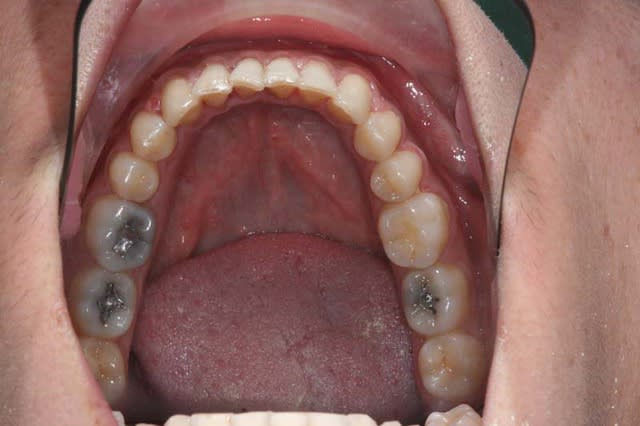

Il et elle me donnent leur accord, voici les photos de départ

je la traite par les techniques de friction faible, et voici le résultat 1 an après

chronologiquement : elle a subi une chir du menton il y a 3 ans, puis insatisfaite du résultat, un traitement O.D.F. de 2 ans, tjs. insatisfaite , elle est allée consulter un 2° chirurgien, c’est alors qu’elle est venue me voir. Les 1° photos datent de cette époque

un an de TTT. en fiction faible, 2° série de photos, elle va aller voir son 2° chirurgien